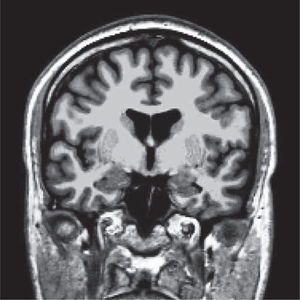

Las alteraciones de la estructura se pueden estudiar más detalladamente utilizando imágenes de resonancia magnética que cubren cada milímetro del cerebro (volumétricas) (Figura 1), desde las cuales es posible separar artificialmente mediante software, las distintas estructuras del cerebro (segmentación) (Figura 2) y poder comparar el tamaño de estas estructuras con una población de sujetos normales de la misma edad. Actualmente es posible obtener volúmenes de cada una de las estructuras como hipocampos, ganglios basales, cerebelo, etc. de nuestro paciente (Figura 3). Además, utilizando esta misma información es posible realizar imágenes tridimensionales del espesor de la corteza cerebral en cada hemisferio (Figura 4).

Segmentación de las distintas estructuras cerebrales de un sujeto normal. Corteza (rojizo), sustancia blanca (derecha: verde, izquierda: blanca), ganglios basales, hipocampos (verde) y amígdalas (celeste).

Software Freesurfer (http://ftp.nmr.mgh.harvard.edu/).